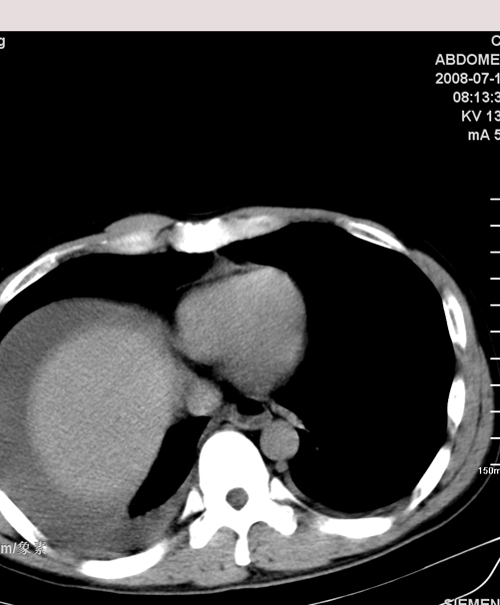

以下是引用muzi888在2008-7-15 10:45:00的发言:[br]大量腹腔积液,气腹,肾皮质弧形高密度影,诊断;1 空腔脏器穿孔 2 右肾包膜下血肿

以下是引用随光逐影在2008-7-15 11:18:00的发言:[br]考虑为:1)腹部空腔脏器穿孔。2)右肾破裂并肾包膜下血肿,肾盂积血。3)腹水(血)。